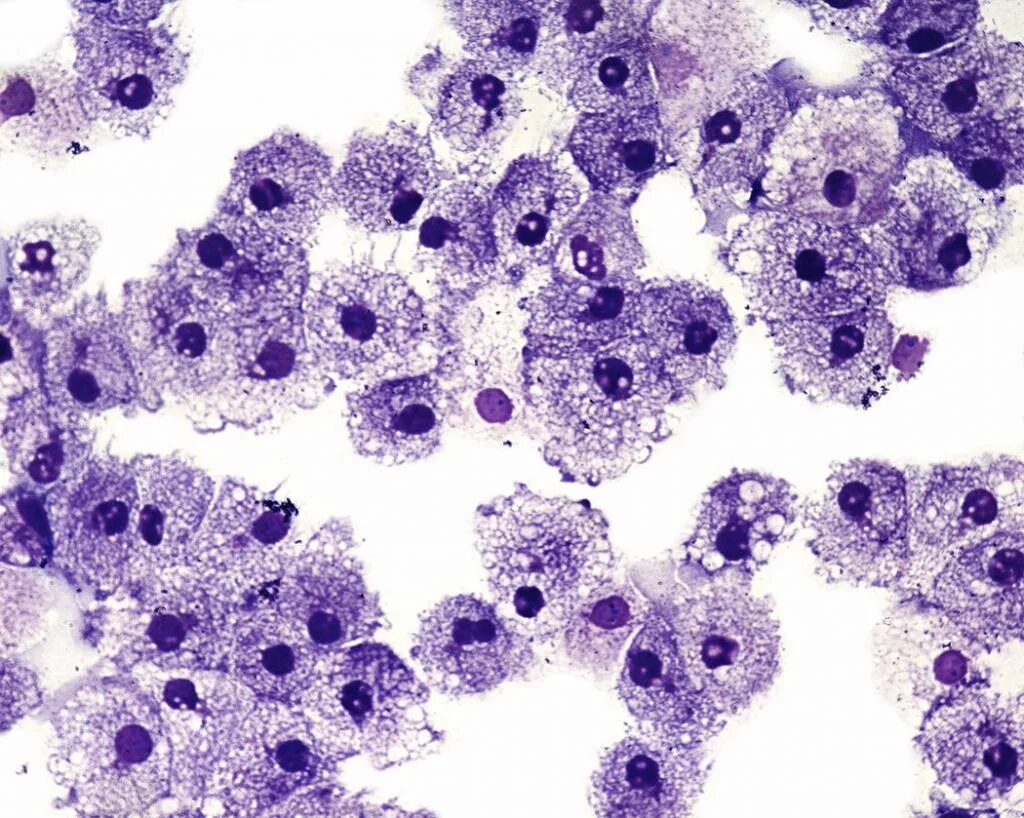

Лейкоциты 50 100